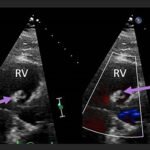

Endovascular coil embolization continues to become a more frequent modality of addressing hemorrhage and bleeding in patients. Migration refers to the coil unraveling or moving from the original embolization site. Migration of a coil is a known complication which can lead to serious consequences based on where the coil migrates. Despite increasing efforts to improve safety and technique, the risk of migration remains. We present a case of an embolization coil that migrated to the right ventricle, which was incidentally found roughly 2 months after undergoing an interventional radiology procedure for gastric variceal bleeding. The patient presented to the emergency department with dyspnea and abdominal pain. Unique images were obtained during his visit and in subsequent follow-up. As use of vascular embolization coils continues to become more commonplace, understanding the risks and complications of these procedures remains an important aspect of providing care for patients once they have left the interventional radiology suite. Coil migration should be a differential to consider in patients who present to the emergency department with signs or symptoms of arrhythmia or pulmonary embolism who have undergone a coil embolization procedure.